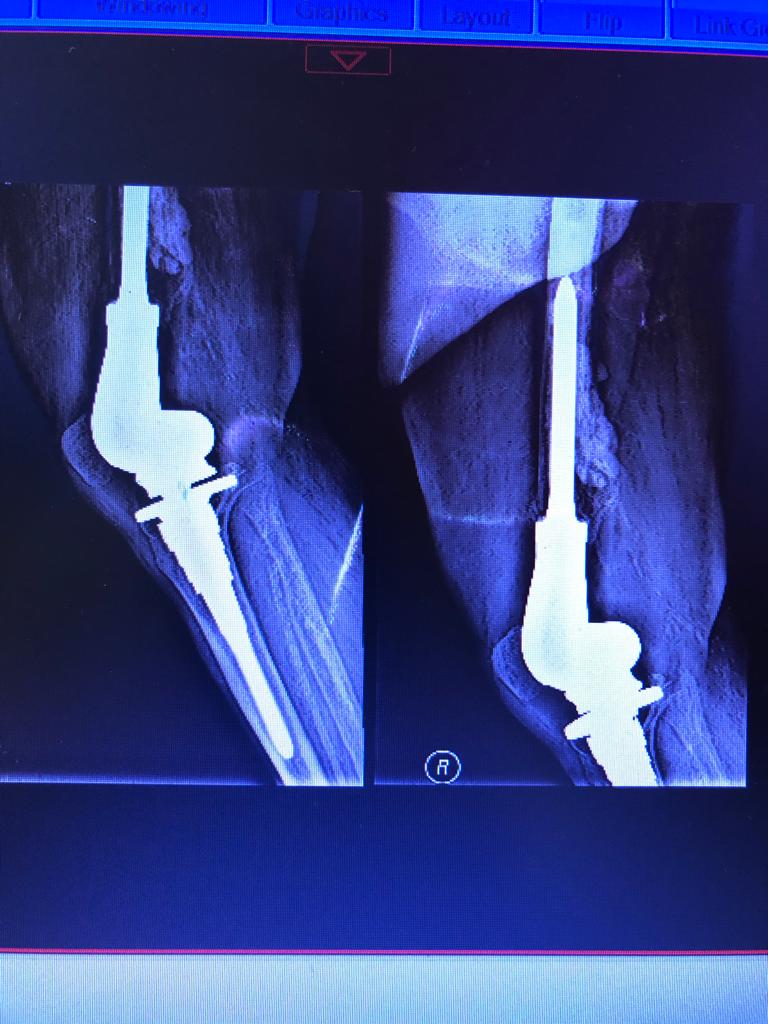

Total Knee Arthroplasty After a non-union